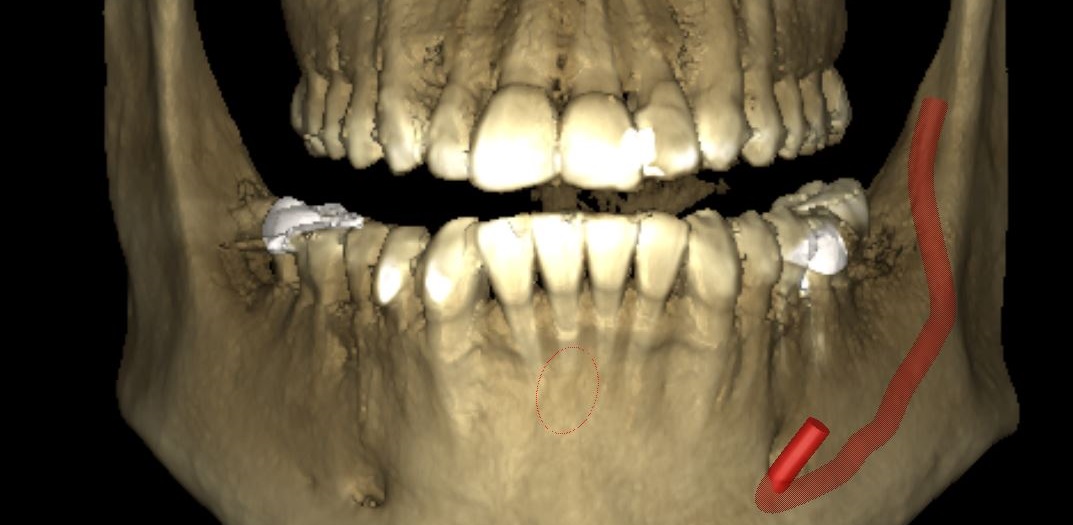

What is CBCT (3D) Imaging Used For?

3D Imaging can be used in a variety of dental procedures, including:

• Dental Implant Placement

• Root Canal Therapy

• Surgery Planning

• Examine the Quality of the Bone Tissue

• Prosthetic Devices

• Disease Diagnosis

• Overdenture

• TMJ Treatment

• Tooth Extractions

We use the best 3D Cone Beam by Planmeca which provides:

Our Planmeca CBCT imaging unit complies with a multitude of diagnostic requirements and provides volumes sizes for every clinical application

We offer CT Scans for our dental patients or as an imaging center for outside patients

Its equipped with a Movement Correction Algorithm

It has a Dedicated Endodontic Imaging mode

Planmeca Ultra Low Doseā„¢ is the leading and scientifically proven method for acquiring CBCT images at a low patient dose

Our Cone Beam offers a seamless imaging workflow and relaxing patient experience due to its open patient positioning